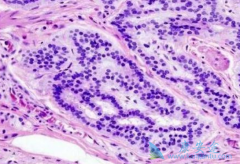

乳腺内有丰富的淋巴管网,淋巴结就是这个管网中的一个个节点,对肿瘤细胞有一定的暂时性的阻隔作用。乳房组织内形成的淋巴液中,约有75%淋巴液依次经过一站站的淋巴结流向同侧腋窝方向,在这个过程中,接受乳房淋巴液的第一站淋巴结(一个或多个)就是前 ...